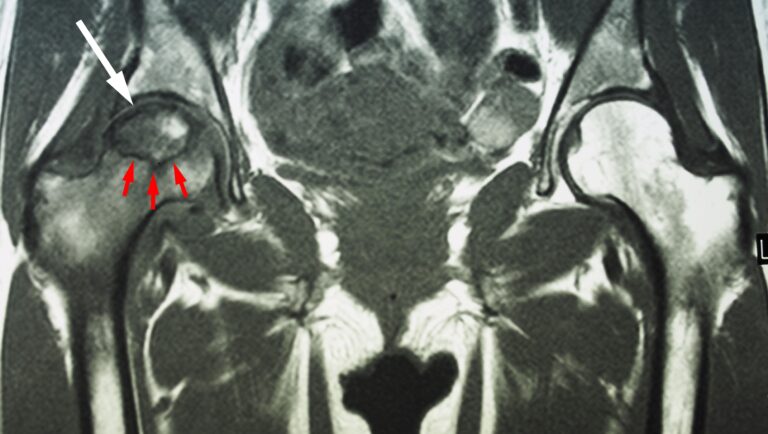

This MRI scan shows osteonecrosis in a patient’s right hip (white arrow). The dark line (red arrows) denotes the border between dead bone and living bone. The patient’s left hip is normal.